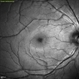

- blue reflectance

- Blue reflectance image of a 30 yo female with PAMM OD.